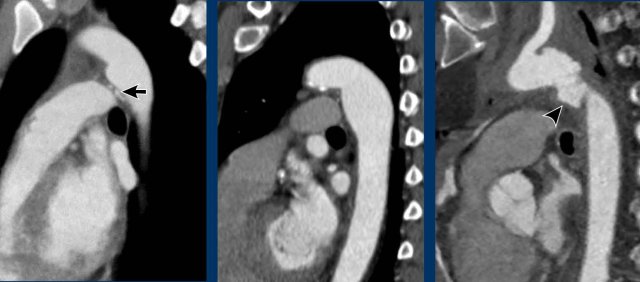

Images

Examples of an aortic diverticulum (left), an aortic splindle (middle), and traumatic aortic injury at the level of the isthmus.

Incidental patent ductus arteriosus (PDA) with a jet of less opacified blood (arrows) into the pulmonary artery.